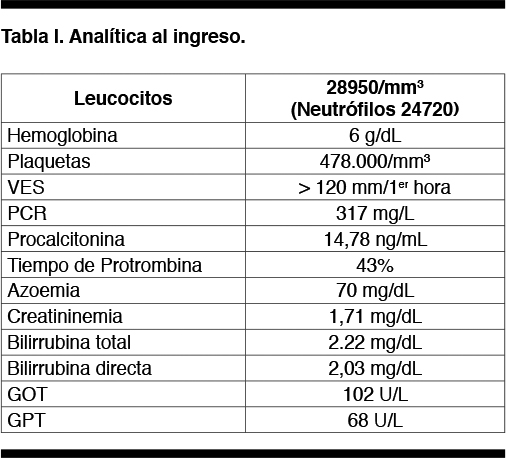

Del examen físico al ingreso se destacamos: febril, hipocoloreado, mal perfundido y con múltiples focos sépticos dentarios. Intenso dolor a la movilización activa y pasiva de los MMII. Sin déficit neurológico. La palpación abdominal evidenciaba dolor difuso a predominio de la FII. Las fosas lumbares estaban dolorosas. Se adjunta tabla con analítica al ingreso (Tabla I).

Se planteó diagnóstico de sepsis a punto de partida de espondilodiscitis piógena, con probable colección abdómino-pelviana. Se realizó TC de columna toraco-lumbo-sacra que confirmó el planteo de espondilodiscitis L1-L2, complicada con abscesos múltiples del psoas (Figuras 1 y 2).